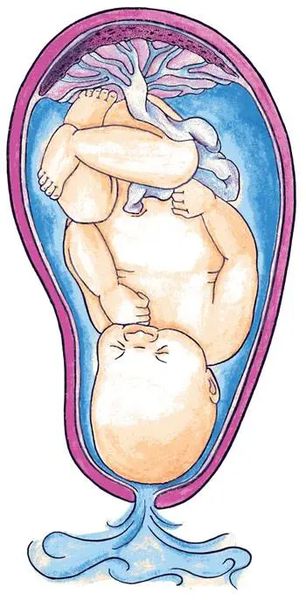

Околоплодный пузырь и плацента: структура и функции